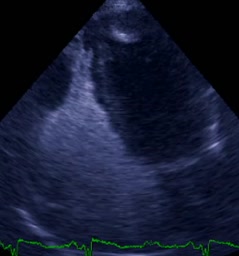

Sezione asse corto modificata grandi vasi. Persistenza di una ampia comunicazione tra l’aorta discendente e l’arteria polmonare sx.